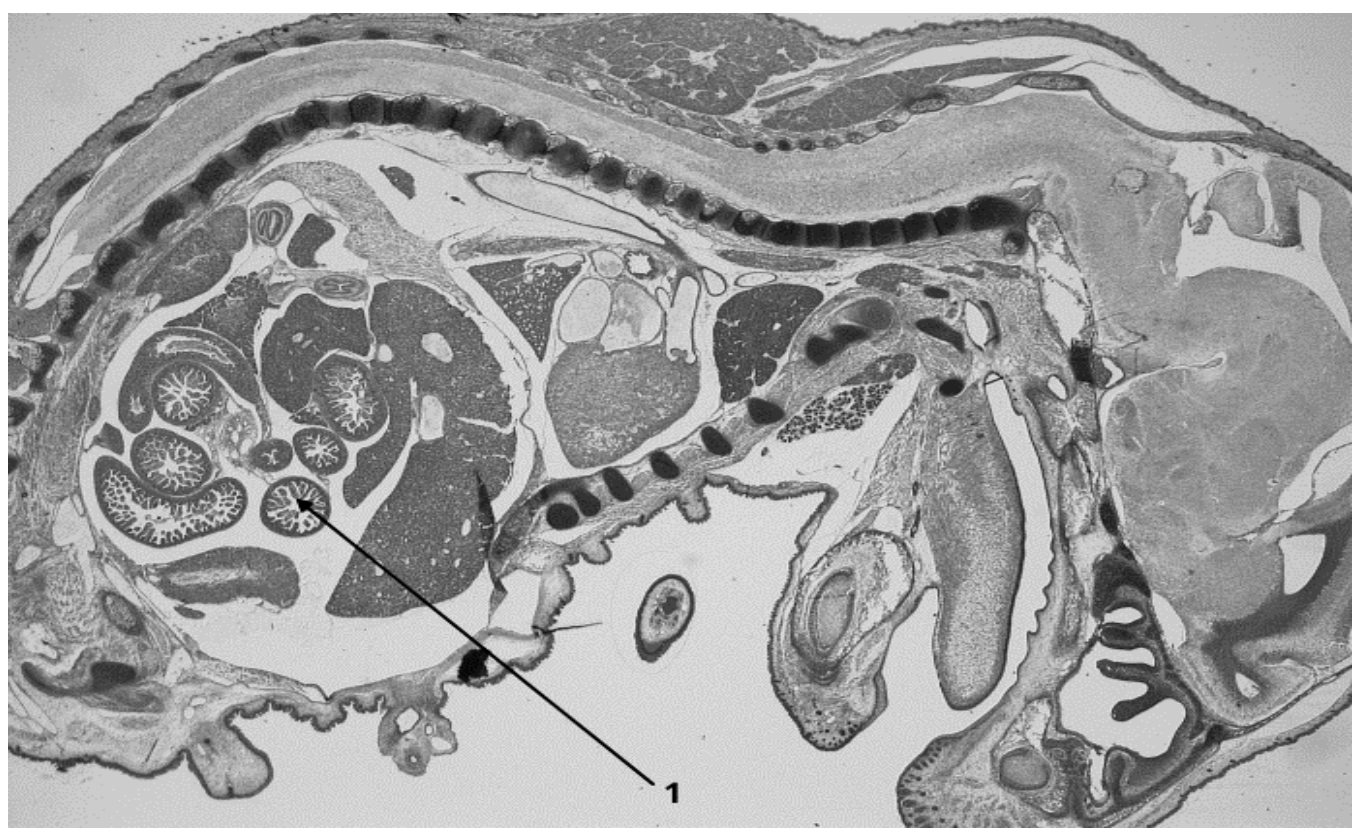

Рассмотрите фотографию гистологического среза. Какой вид эпителия встречается там, куда указывает стрелка?